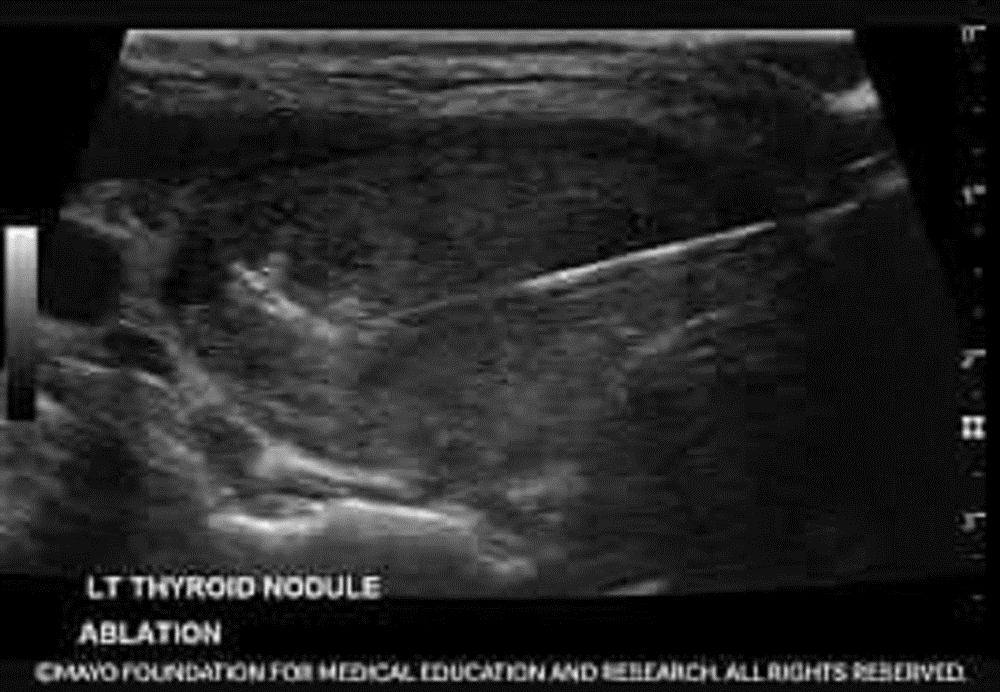

Siêu âm tuyến giáp là phương tiện đầu tay, rẻ tiền, an toàn để phát hiện sớm u tuyến giáp từ khi u còn rất nhỏ, không có triệu chứng gì. Siêu âm đầu dò chuyên dụng đặc biệt là siêu âm đàn hồi mô có thể chẩn đoán phân độ nguy cơ ung thư ác tính của khối u. Qua đó sẽ có chỉ định những u nào nguy cơ cao ác tính nên xét nghiệm chọc hút tế bào để làm rõ chẩn đoán, những u nào nguy cơ ác tính rất thấp chưa cần sinh thiết tế bào mà chỉ cần theo dõi định kì.

Hình ảnh siêu âm ở bệnh nhân ung thư tuyến giáp